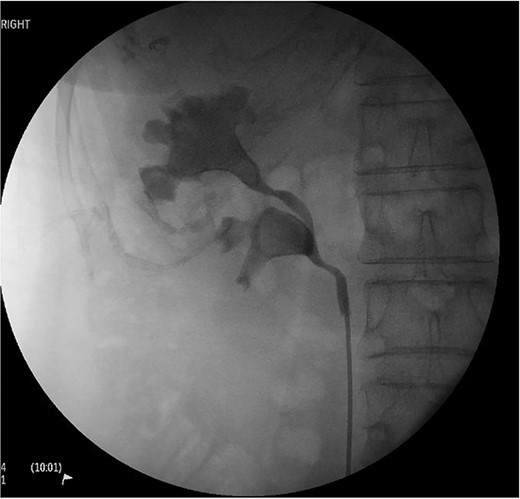

A 71-year-old female presented with urosepsis, right flank pain and a history of recurrent UTIs. CTKUB noting large right-sided staghorn calculi within the superior pole and renal pelvis without dilatation. Retrograde pyelogram further demonstrating bifid renal pelvis (Fig. 1). She was treated for Pseudomonas aeruginosa with IV piperacillin-tazobactam, and prepared for inpatient definitive management. Pre-operative creatinine was 65 umol/L, and haemoglobin 130 g/L.

Right retrograde pyelogram as part of pre-operative workup and diagnosis. Evidence of a proximal bifid ureter with distal confluence can be seen, and the presence of two large staghorn calculi are clearly seen in both the upper and lower moity renal pelvis.